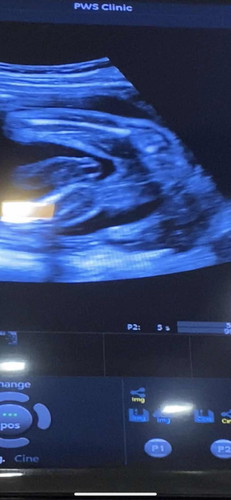

น้องเป็นผู้หญิงใช่มั้ยคะ

น้องเป็นผู้หญิงใช่มั้ยคะ มีโอกาสเป็นผู้ชายมั้ยคะ อยากซื้อของเตรียมให้น้องเเล้วค่ะ💖

เหมือนผู้หญิงนะคะ

น่าจะหญิงค่ะแม่

น่าจะหญิงนะค่ะ

ผู้หญิงค่ะ

หญิงค่ะ